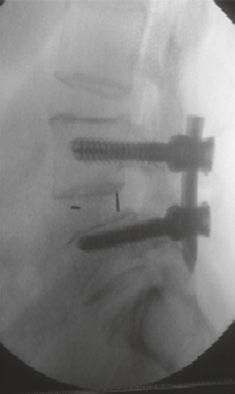

在过去的十年中,TLIF(经椎间孔腰椎椎体间融合)已经成为实现节段性椎体间融合的流行技术。最小通路技术的最新进展有助于通过微创方法进行手术,并提供充分的减压和固体融合。微创技术也有助于避免传统的后路开放入路[1,2]的许多缺点。Schwender等人[3]的一项研究报告了在接受微创TLIF手术的患者的视觉模拟评分和奥斯威特残疾指数评分有临床显著改善,100%的融合率为100%。在MIS病例中,通过更小更窄的解剖进行可视化。退行性脊柱侧弯存在复杂的脊柱病理,如脊柱旋转、透视镜解剖不良、椎弓根不对称和形状异常的椎弓根,可对MIS-TLIF构成严重挑战,导致椎弓根螺钉和钛笼[4]放置不正确。脊柱手术中的图像引导导航对MIS外科医生是一个宝贵的帮助,因为它允许更大的区域。透视可以帮助螺钉放置;然而,它增加了手术时间和辐射暴露给外科医生和手术室人员。据报道,徒手和透视引导下椎弓根螺钉置入时,腰椎移位率高达30%,胸椎移位率高达50%。mal定位的螺钉可能对脊髓、神经根和大血管造成潜在的损伤,也会降低脱位的稳定性。医学法律上对患者安全的担忧进一步加强了图像引导螺钉放置的必要性,以提高[5]的准确性。

计算机辅助脊柱手术(CASS)是一门使用新的基于计算机的技术的学科,包括立体定向、导航手术和机器人技术。导航辅助脊柱手术是一组技术,它允许外科医生在手术中获取与手术器械相关的实时、三维和虚拟的脊柱图像。